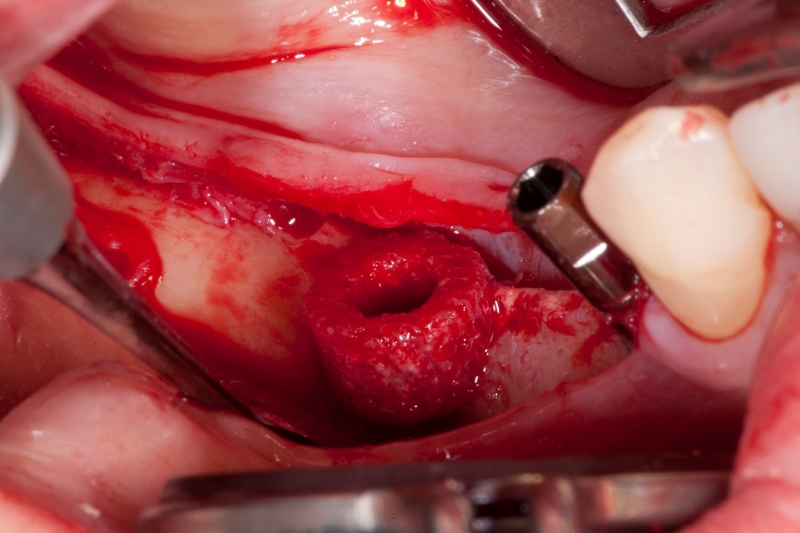

09/18 - Sinus cavity, Schneiderian membrane is mobilized

Vertical augmentation & sinus lift with maxgraft® bonering - Dr. O. Yüksel and Dr. B. Giesenhagen